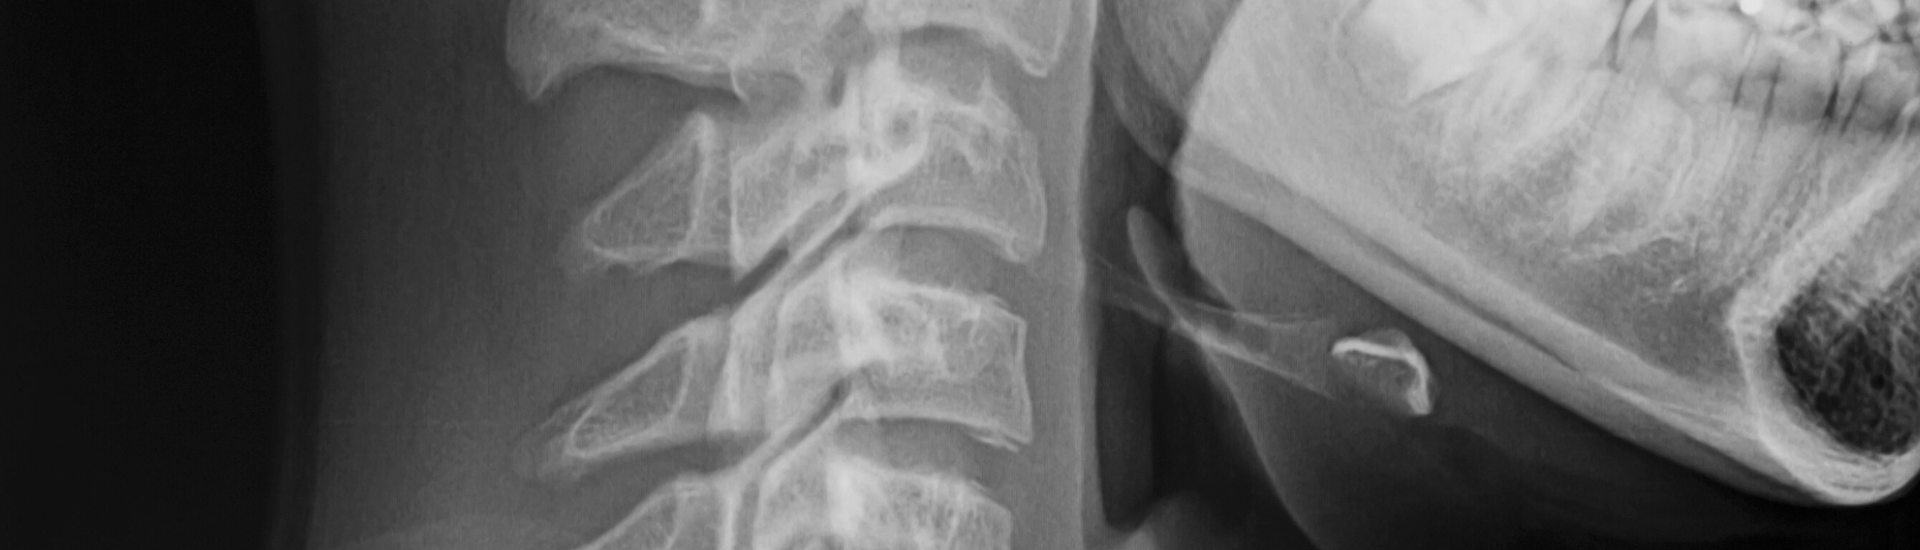

La RX Rinofaringe è un esame diagnostico non invasivo che permette di ottenere immagini dettagliate della rinofaringe, ossia la parte posteriore della cavità nasale. Presso il Poliambulatorio S-Medical Group di Sora, questo esame viene eseguito con apparecchiature all’avanguardia e da professionisti esperti, garantendo un elevato standard di sicurezza e precisione diagnostica. L’utilizzo di raggi X a bassa dose consente di individuare eventuali anomalie o patologie nella zona, aiutando i medici a definire un trattamento personalizzato.

La RX Rinofaringe è una radiografia mirata che utilizza una bassa dose di radiazioni per creare immagini dettagliate della rinofaringe. Al Poliambulatorio S-Medical Group di Sora, l’esame si svolge in un ambiente sicuro e confortevole. Il paziente viene posizionato di fronte all’apparecchio radiologico, e il tecnico esegue l’acquisizione delle immagini in pochi minuti. Grazie alla qualità delle nostre apparecchiature, siamo in grado di fornire risultati precisi e chiari.

Grazie all’RX Rinofaringe, è possibile osservare con precisione le ossa, i tessuti molli e le strutture della rinofaringe. Al Poliambulatorio S-Medical Group di Sora, i medici analizzano attentamente le immagini per rilevare eventuali alterazioni anatomiche e anomalie, quali infiammazioni, lesioni o altre condizioni patologiche che possono influire sulla funzionalità respiratoria.

La RX Rinofaringe utilizza radiazioni a bassa intensità, il che la rende sicura e ben tollerata dalla maggior parte dei pazienti. Al Poliambulatorio S-Medical Group di Sora, adottiamo tutte le misure necessarie per proteggere il paziente, riducendo al minimo l’esposizione e utilizzando tecniche di schermatura per garantire la massima sicurezza durante l’esecuzione dell’esame.